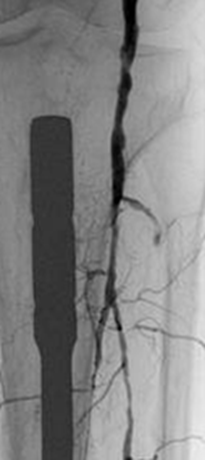

Resultado tras la activación del catéter Xpeedior® de AngioJet® durante 160 s (técnica Rapid Lysis con Alteplase) que muestra la arteria poplítea patente y la estenosis crítica.